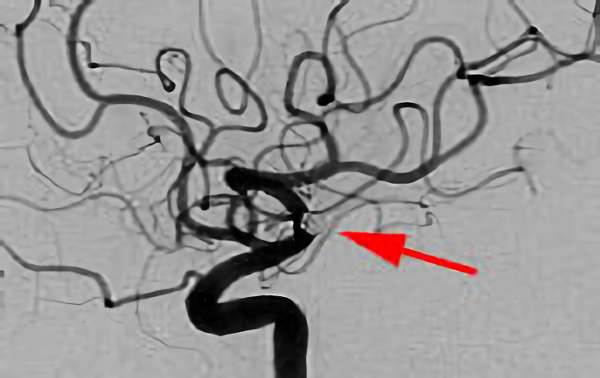

No.1600 手術前

No.1600 手術中

No.1600 手術後

'25年12月

くも膜下出血

脳底動脈瘤破裂

40代

救急外来